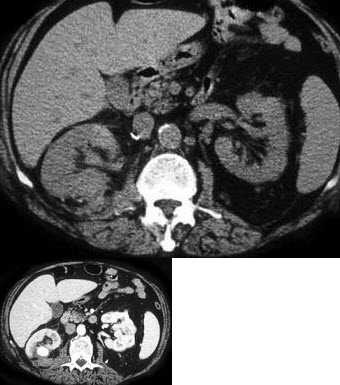

细节方面,CT理论整理可不能光靠死记硬背。俺记得第一次接触时,那些公式和算法让俺头大如斗,但后来通过实际操作,才摸清了门道。比如,在扫描胸部时,调整毫安秒和千伏值这些参数,能大幅提升图像质量,减少辐射伤害——这可是理论里的精髓!您要是整理时,不妨加入个人笔记,记录下自己的感受:比如“这个重建算法真妙,像拼图一样把碎片合成完整图像”,或者“辐射防护知识得牢记,安全比啥都重要”。这种情绪化表达,让学习变得生动,反而不容易忘。再说,现在人工智能也掺和进来了,但基础理论仍是根基,整理时得把新旧知识融合,比如比较传统CT与螺旋CT的差异,这样才足,让您始终走在行业前沿。